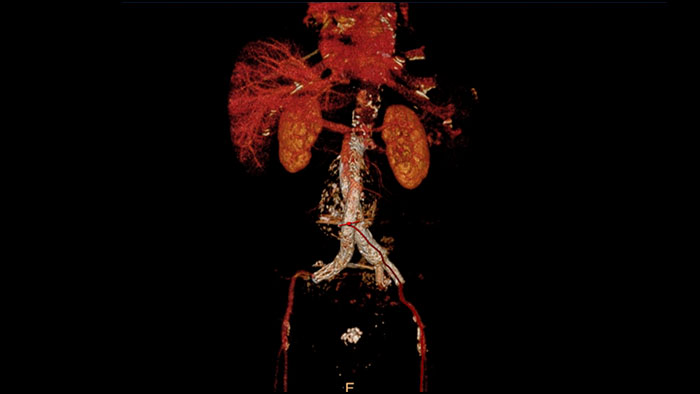

Comprehensive vascular analysis planning

Designed to examine and quantify different types of vascular lesions from CTA and MRA scans. It accommodates different modes of inspection, allows labeling different vascular lesions, and helps navigating through multiple findings. Demonstrated to reduce the post-processing time by 50% when compared to manual Head & Neck CT angiography (CTA) analysis*.